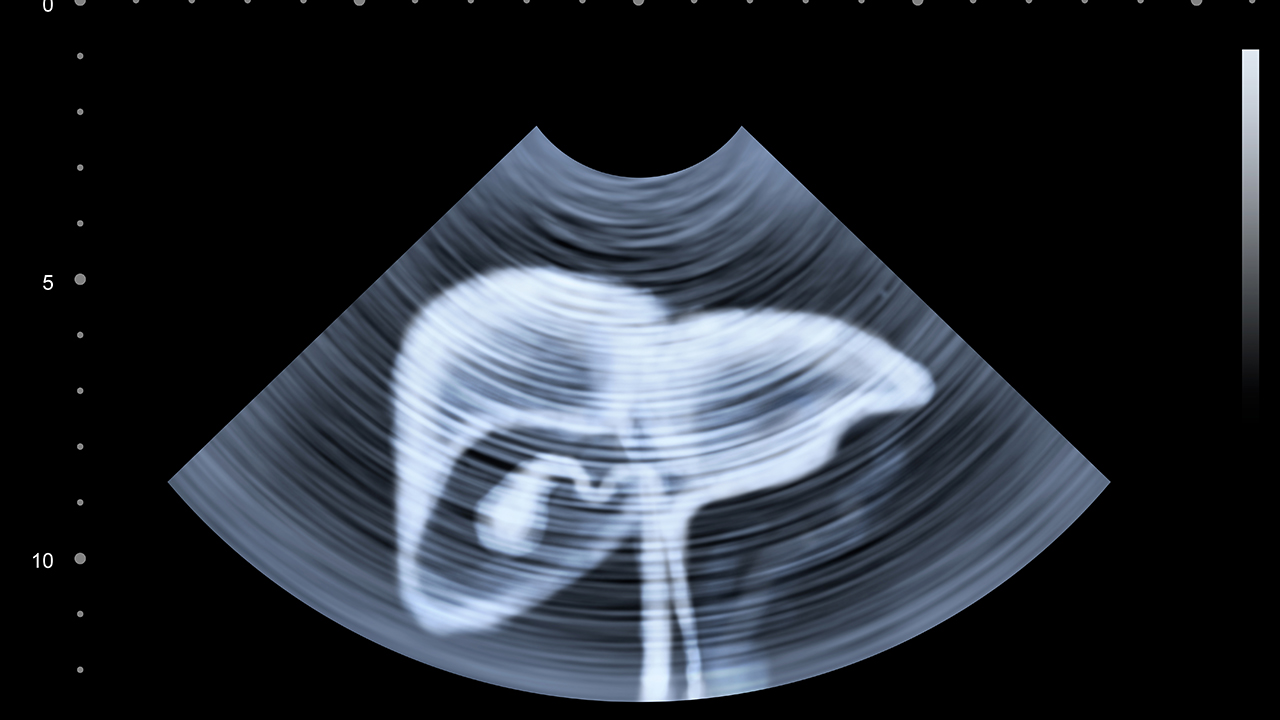

肝癌晚期的预防与健康管理至关重要。对于高风险人群,如慢性肝炎、肝硬化患者,应定期进行肝脏超声和甲胎蛋白检测,以便早期发现病变。日常生活中应避免饮酒、减少高脂肪饮食,保持规律作息。对于已确诊的患者,应积极配合医生治疗,保持良好的心态,适当进行轻体力活动,增强免疫力。中医药在调理体质、减轻放化疗方面具有一定优势,可作为辅助治疗手段。